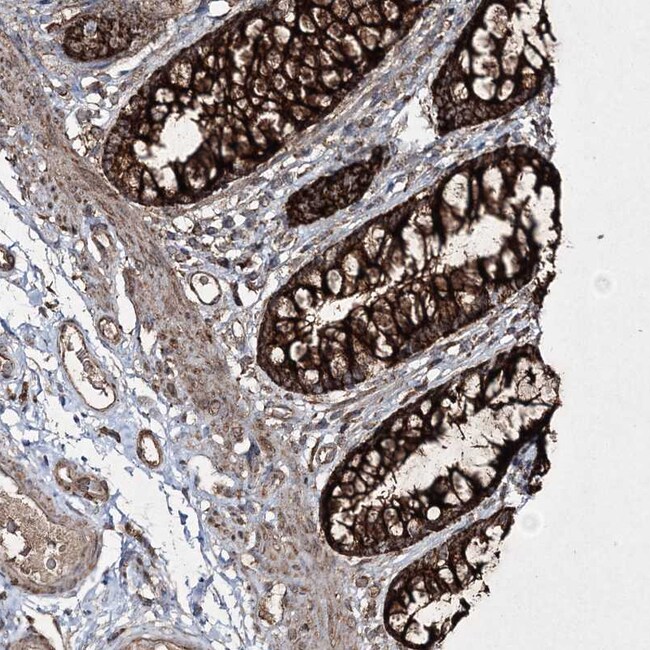

| Applications | Immunohistochemistry (Paraffin), Western Blot, Immunocytochemistry |